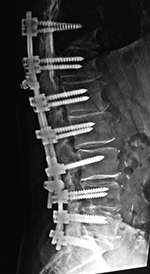

| Pedicle fixation screws and rods |

| 20 year-old woman with L1 vertebral body compression fracture treated with T12-L2 posterior spinal fusion using pedicle screws at T12 and L2 with connecting rods on each side. |